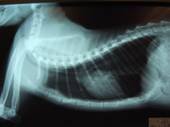

手術後2ヶ月。一般状態は非常に良好である。

レントゲンでも再発なく、非常に良好な状態である。

手術前のレントゲンとくらべ、心臓もはっきり描出されている。